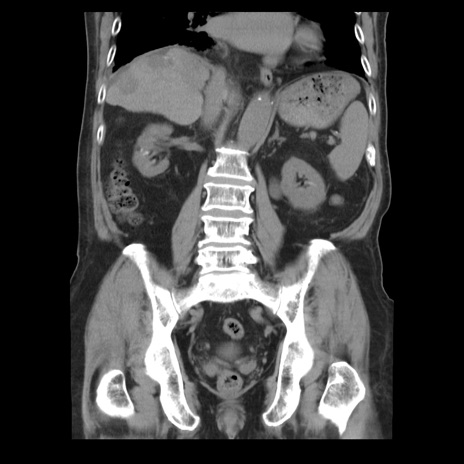

症例21(冠状断像)

【症例】70歳代男性

【主訴】腹痛

【現病歴】肝硬変・肝細胞癌にてかかりつけの方。約9時間前に食後より腹痛出現。症状が徐々に増悪し、嘔吐出現したため来院。

【既往歴】肝硬変、肝細胞癌(RFA、TACE後)

【身体所見】意識清明、表情苦悶様、BT 36℃、BP 129/78mmHg、P 88bpm、SpO2 97%(RA)、右上腹部から心窩部にかけて圧痛あり、反跳痛なし、筋性防御あり。

【データ】WBC 5800、CRP 0.16